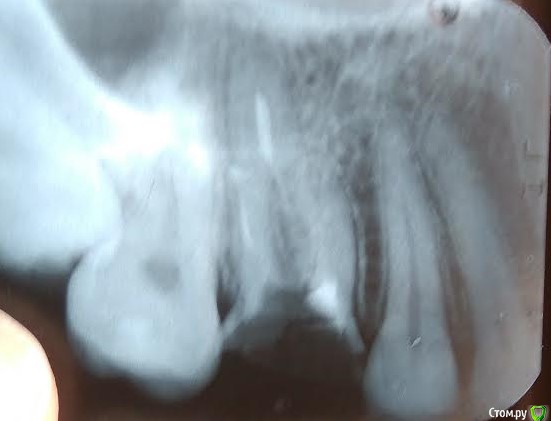

AlenaBeg Опубликовано 12 января, 2017 Поделиться Опубликовано 12 января, 2017 Добрый день.Во время беременности перелечивала зуб верхнюю 6ку (вроде 26 по номеру), коронковая часть была значительно разрушена (не было большей половины одной стенки), врач поставил в канал штифт и нарастил коронковую часть зуба. Снимки после лечения не делали по понятной причине. Через 5 лет часть маленькая часть пломбы откололась, я пошла ставить коронку на зуб к другому врачу (первый врач, у которого был удачно пролечен не один зуб переехал). Врач сказал, что каналы запломбированы не до конца, вскрыл зуб, перепломбировал 2 канала, отметил, что третий канал непроходим и нужно проводить депофорез. Во время чистки каналов сильно кровило, врач сказал, что немного травмировал десну. Предстояло 3 процедуры депофореза с интервалом в 2 недели между ними. После первой процедуры было чувство распирания в зубе и периодическая боль в течение пары дней. После второй распирание и боль усилились, длились около недели. К третей процедуре боли не было, но было болезненно прикасаться к зубу со стороны щеки, ближе к соседнему зубу (5). Было ощущение, что маленький кусочек зуба будто шатается. Очень испугалась, решив, что сломался корень зуба. Рассказав это лечащему врачу, он отправил меня на снимок, сказал, что действительно скололась небольшая часть зуба и перед постановкой вкладки и коронки мне ее просто уберут, с корнем все в порядке. С третьей пломбой я ходила около 4х недель, т.к. врач был на больничном. После снятия временной пломбы оказалось, что сильно воспалена десна, врач сказал, что это реакция на длительное хождение со временной пломбой, и все заживет в течение полу года. В этот же день я была направленна в ортопедическое отделение. Врач, взглянув на снимок, сказала, что зуб под удаление, почему не сказала, только что как минимум есть непроходимый канал. Удивлению не было предела. После разговора с лечащим врачом и заведующей терапевтического отделения меня перенаправили к другому ортопеду. Пришлось снова ходить с временной пломбой дней пять. Вот тут началась ужастная боль со всей стороны наружней стенки зуба (со стороны щеки), невозможно было ничем прикоснуться к ней, сразу появлялась резкая боль, напоминающая боль при гематоме. На приеме ортопеда (по плану была установка вкладки) я обо всем оповестила врача. Он снял пломбу, но болевые ощущения при касании этой стенки зуба были очень сильны. Врач сказал, что от временной пломбы произошло расширение зуба, и нужно немного дать отдохнуть зубу. Врач спилил коронковую часть зуба, поставил фотопломбу и назначил прием через 10 дней. Над самим зубом рядом с соседним (5) нависала ярко красная десна, которая болела, если ее заденешь (посмотреть это мне удалось при помощи стоматологического зеркала). Зуб со стороны щеки также болел, если постучать по нему. Боль странная, сразу проходит, если зуб не трогать, но при постукивании будто чувствуются шевеления зуба. К дате приема я заболела, прием пришлось перенести. Десна, нависающая над зубом, перестала болеть, стала не такой красно, но не исчезла. При постукивании осталась чувствительность в маленьком кусочку зуба рядом с 5кой, не такая ярко выраженная, как раньше. Пока дождусь приема лечащего врача, с ума сойду. Не покидают меня мысли, что с зубом что-то не так.Вопросы:1. Есть снимки зуба до, во время и после лечения. На последних мне мерещится трещина в корне, где был проведен депофорез. Очень прошу посмотреть. Возможно, нет смысла пытаться ставить вкладку и коронку.2. Как десна (или это даже не десна) оказалась на коронковой части зуба? Куда она денется потом? Спасибо! По поводу снимков. Я уже поняла, что фотографировала неправильно. Проблемный зуб с левой стороны. Но так как первых двух снимков (до лечения и перед депофорезом) на руках нет, потерялись у врача, хорошо, что успела сделать фотографии, последние 2 сфотографировала также. Они есть у меня. Ссылка на комментарий

AlenaBeg Опубликовано 12 января, 2017 Автор Поделиться Опубликовано 12 января, 2017 На прием ко врачу обязательно пойду после полного выздоровления. А по снимкам совсем ничего не видно? На последнем на корне, где непроходимый канал, как будто трещина. Ссылка на комментарий

red_butler Опубликовано 12 января, 2017 Поделиться Опубликовано 12 января, 2017 А по снимкам совсем ничего не видно? по снимкам зуб требует повторного лечения корневых каналов, депофорез таковым не является. Но главное это объем сохраненных твердых тканей, если его недостаточно, или есть трещина то зуб удалять Ссылка на комментарий